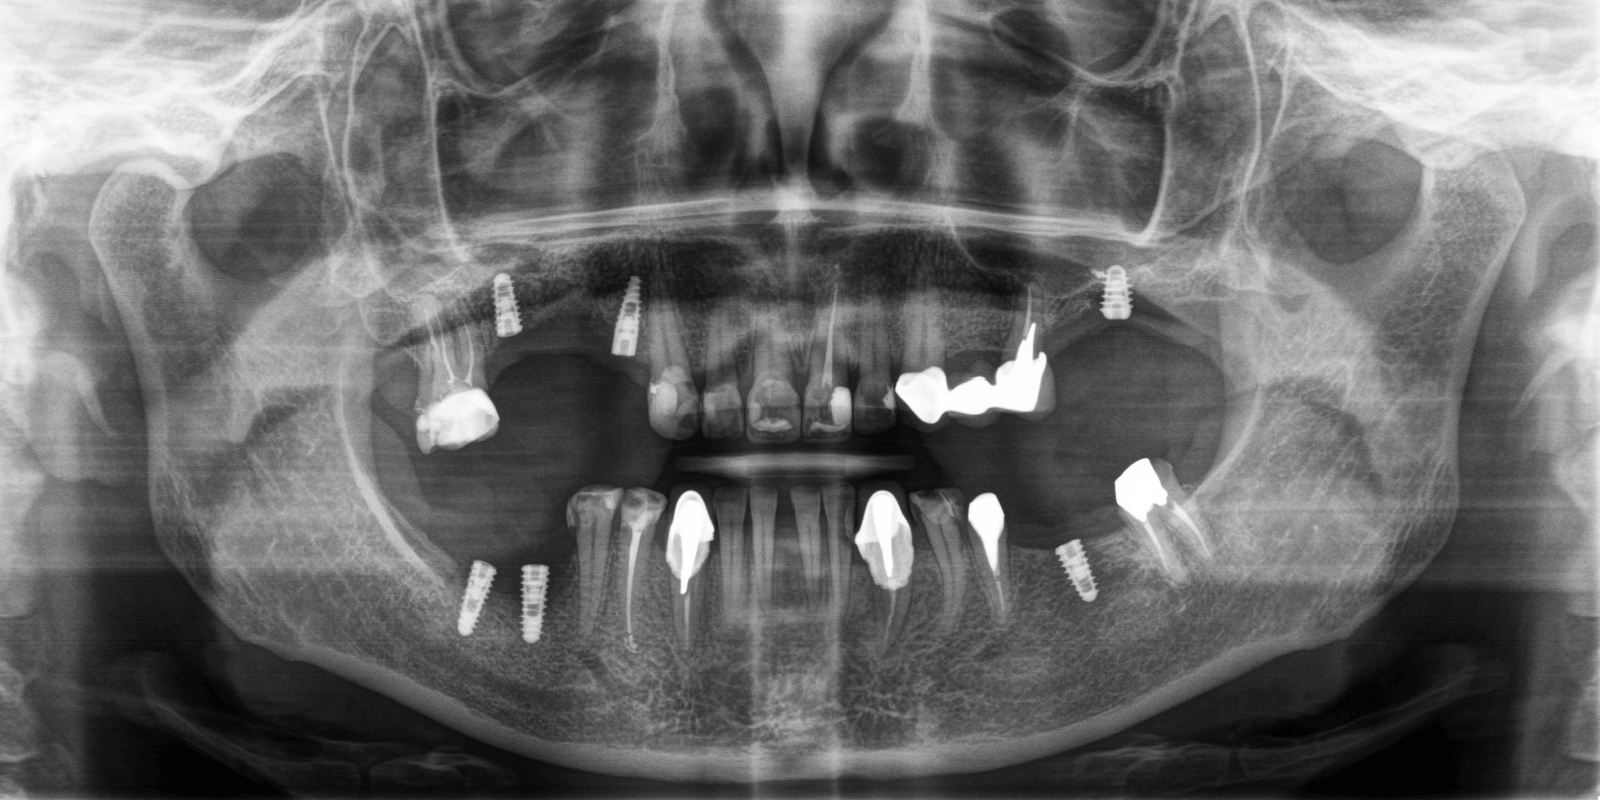

- Одноэтапно установить зубные импланты в области зубов 2.6, 3.6, 4.6, 4.7.

- Ортопедическим методом поднять зубной прикус для предотвращения дальнейшего разрушения зубного ряда и с целью снятия нагрузки на суставы.